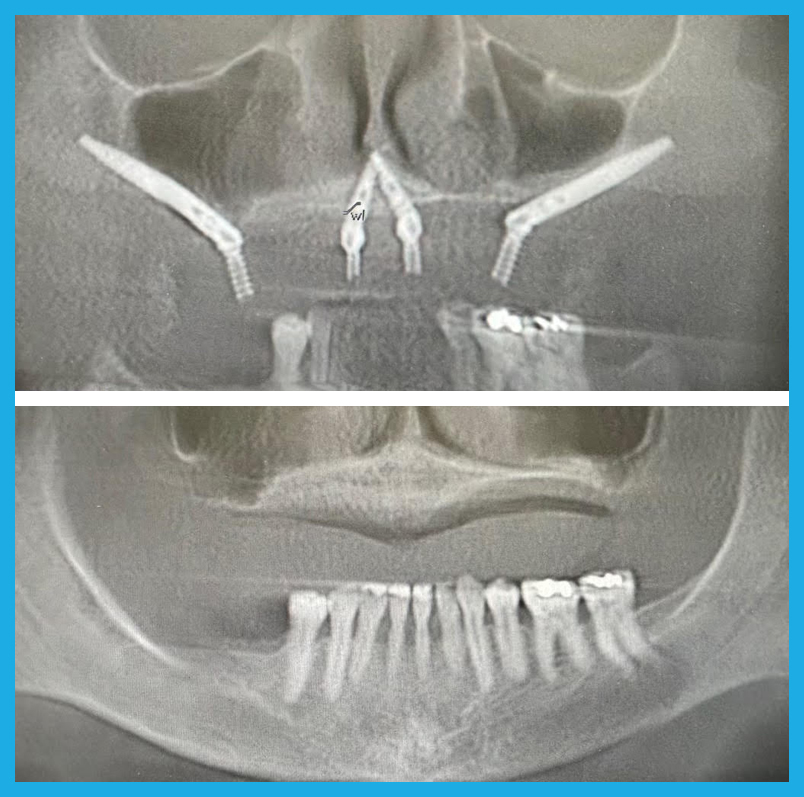

A Lifeline for Patients with Severe Bone Loss

Zygomatic Implants, also known as no-bone implants, are the ultimate solution for patients who have been told they don’t have enough bone for traditional dental implants. This highly specialized procedure is designed for individuals with severe bone loss, and it requires an extraordinary level of skill and experience. At OneSolution® Dental Implant Centers, we are among the very few in the country with the expertise to perform this life-changing procedure.

- Zygomatic and Pterygoid Implants: A Faster Solution: Traditional dental implant methods often require extensive bone grafting and a lengthy healing period, sometimes taking up to a year before final teeth are placed. Zygomatic and Pterygoid Implants bypass the need for bone grafts by anchoring the implants in the cheekbone and pterygoid plate, allowing for immediate loading of teeth. This not only shortens the treatment time dramatically but also provides a solution for patients who were previously told they weren’t candidates for implants due to severe bone loss.

Before and After

Zygomatic Implants